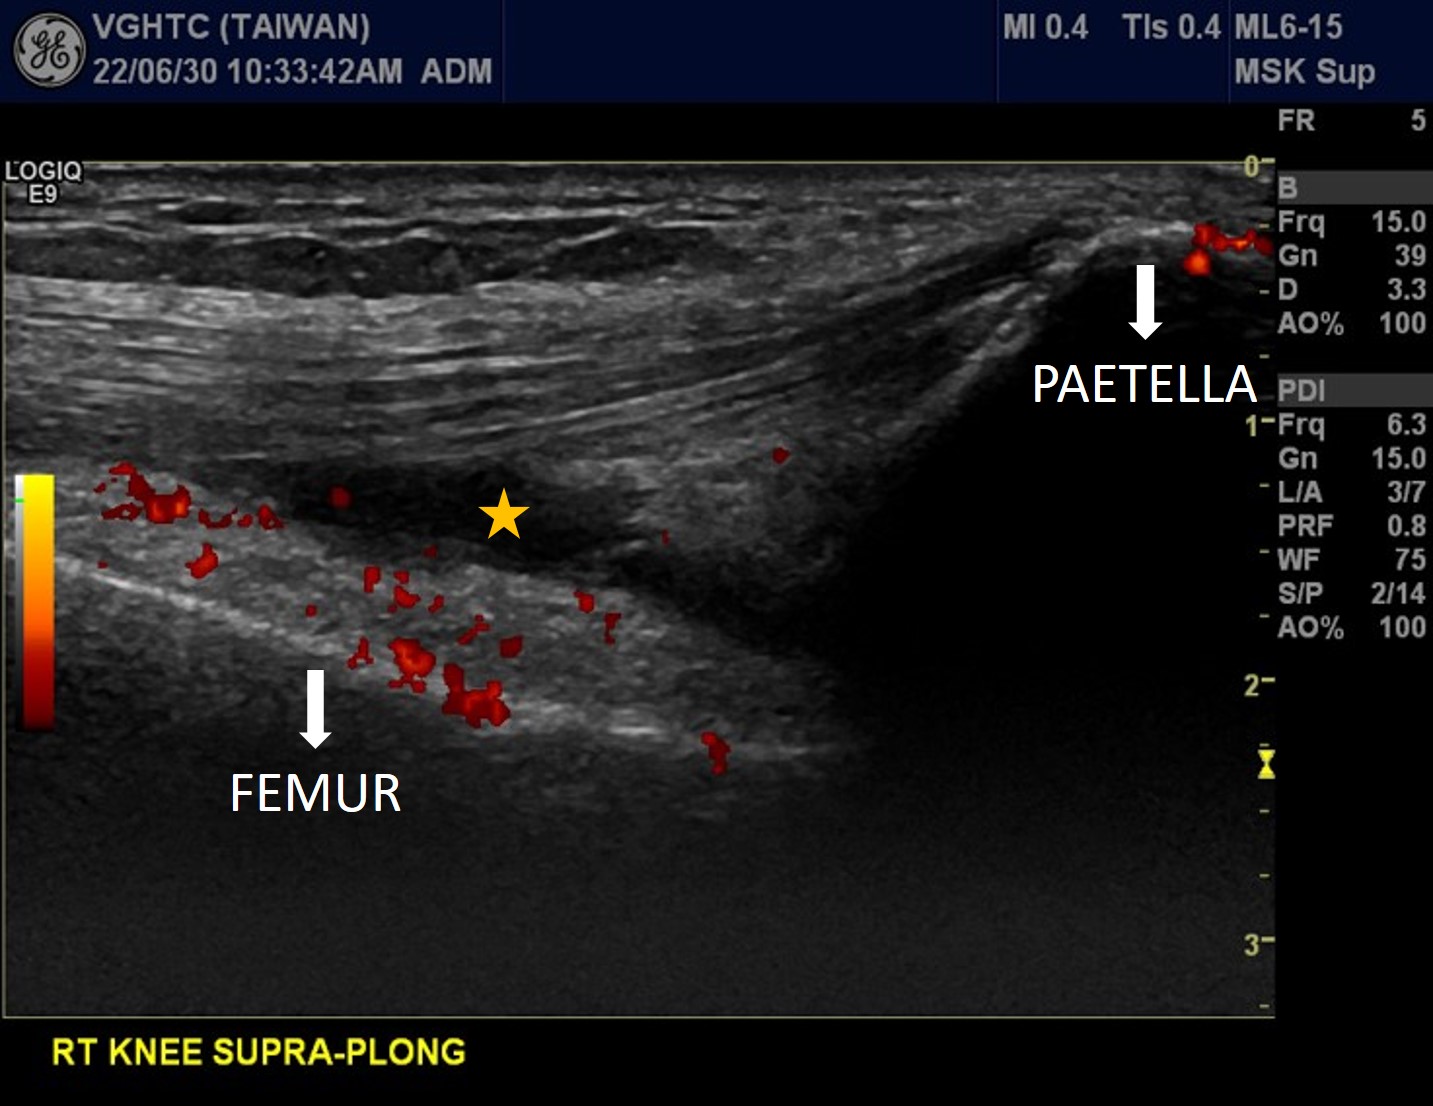

Longitudinal scan at suprapetellar region of right knee with power Doppler ultrasound showed increased joint effusion (asterisks in Picuture 6 ). Posterior longitudinal scan of right elbow with power Doppler ultrasound showed increased joint effusion at olecranon fossa (asterisks in Picutre 7) with hypervascularity (red color signal), indicating active arthritis of right elbow. Dorsal longitudinal scan at left MTP1 showed synovial hypertrophy with heterogeneous echogenicity , possible crystal deposition. (Picuture 8). Dorsal longitudinal scan with power Doppler ultrasound at right MCP3 showed synovial hypertrophy with hypervascularity (red color signal in Picture 9), indicating active arthritis.

Picuture 6. Rt Knee